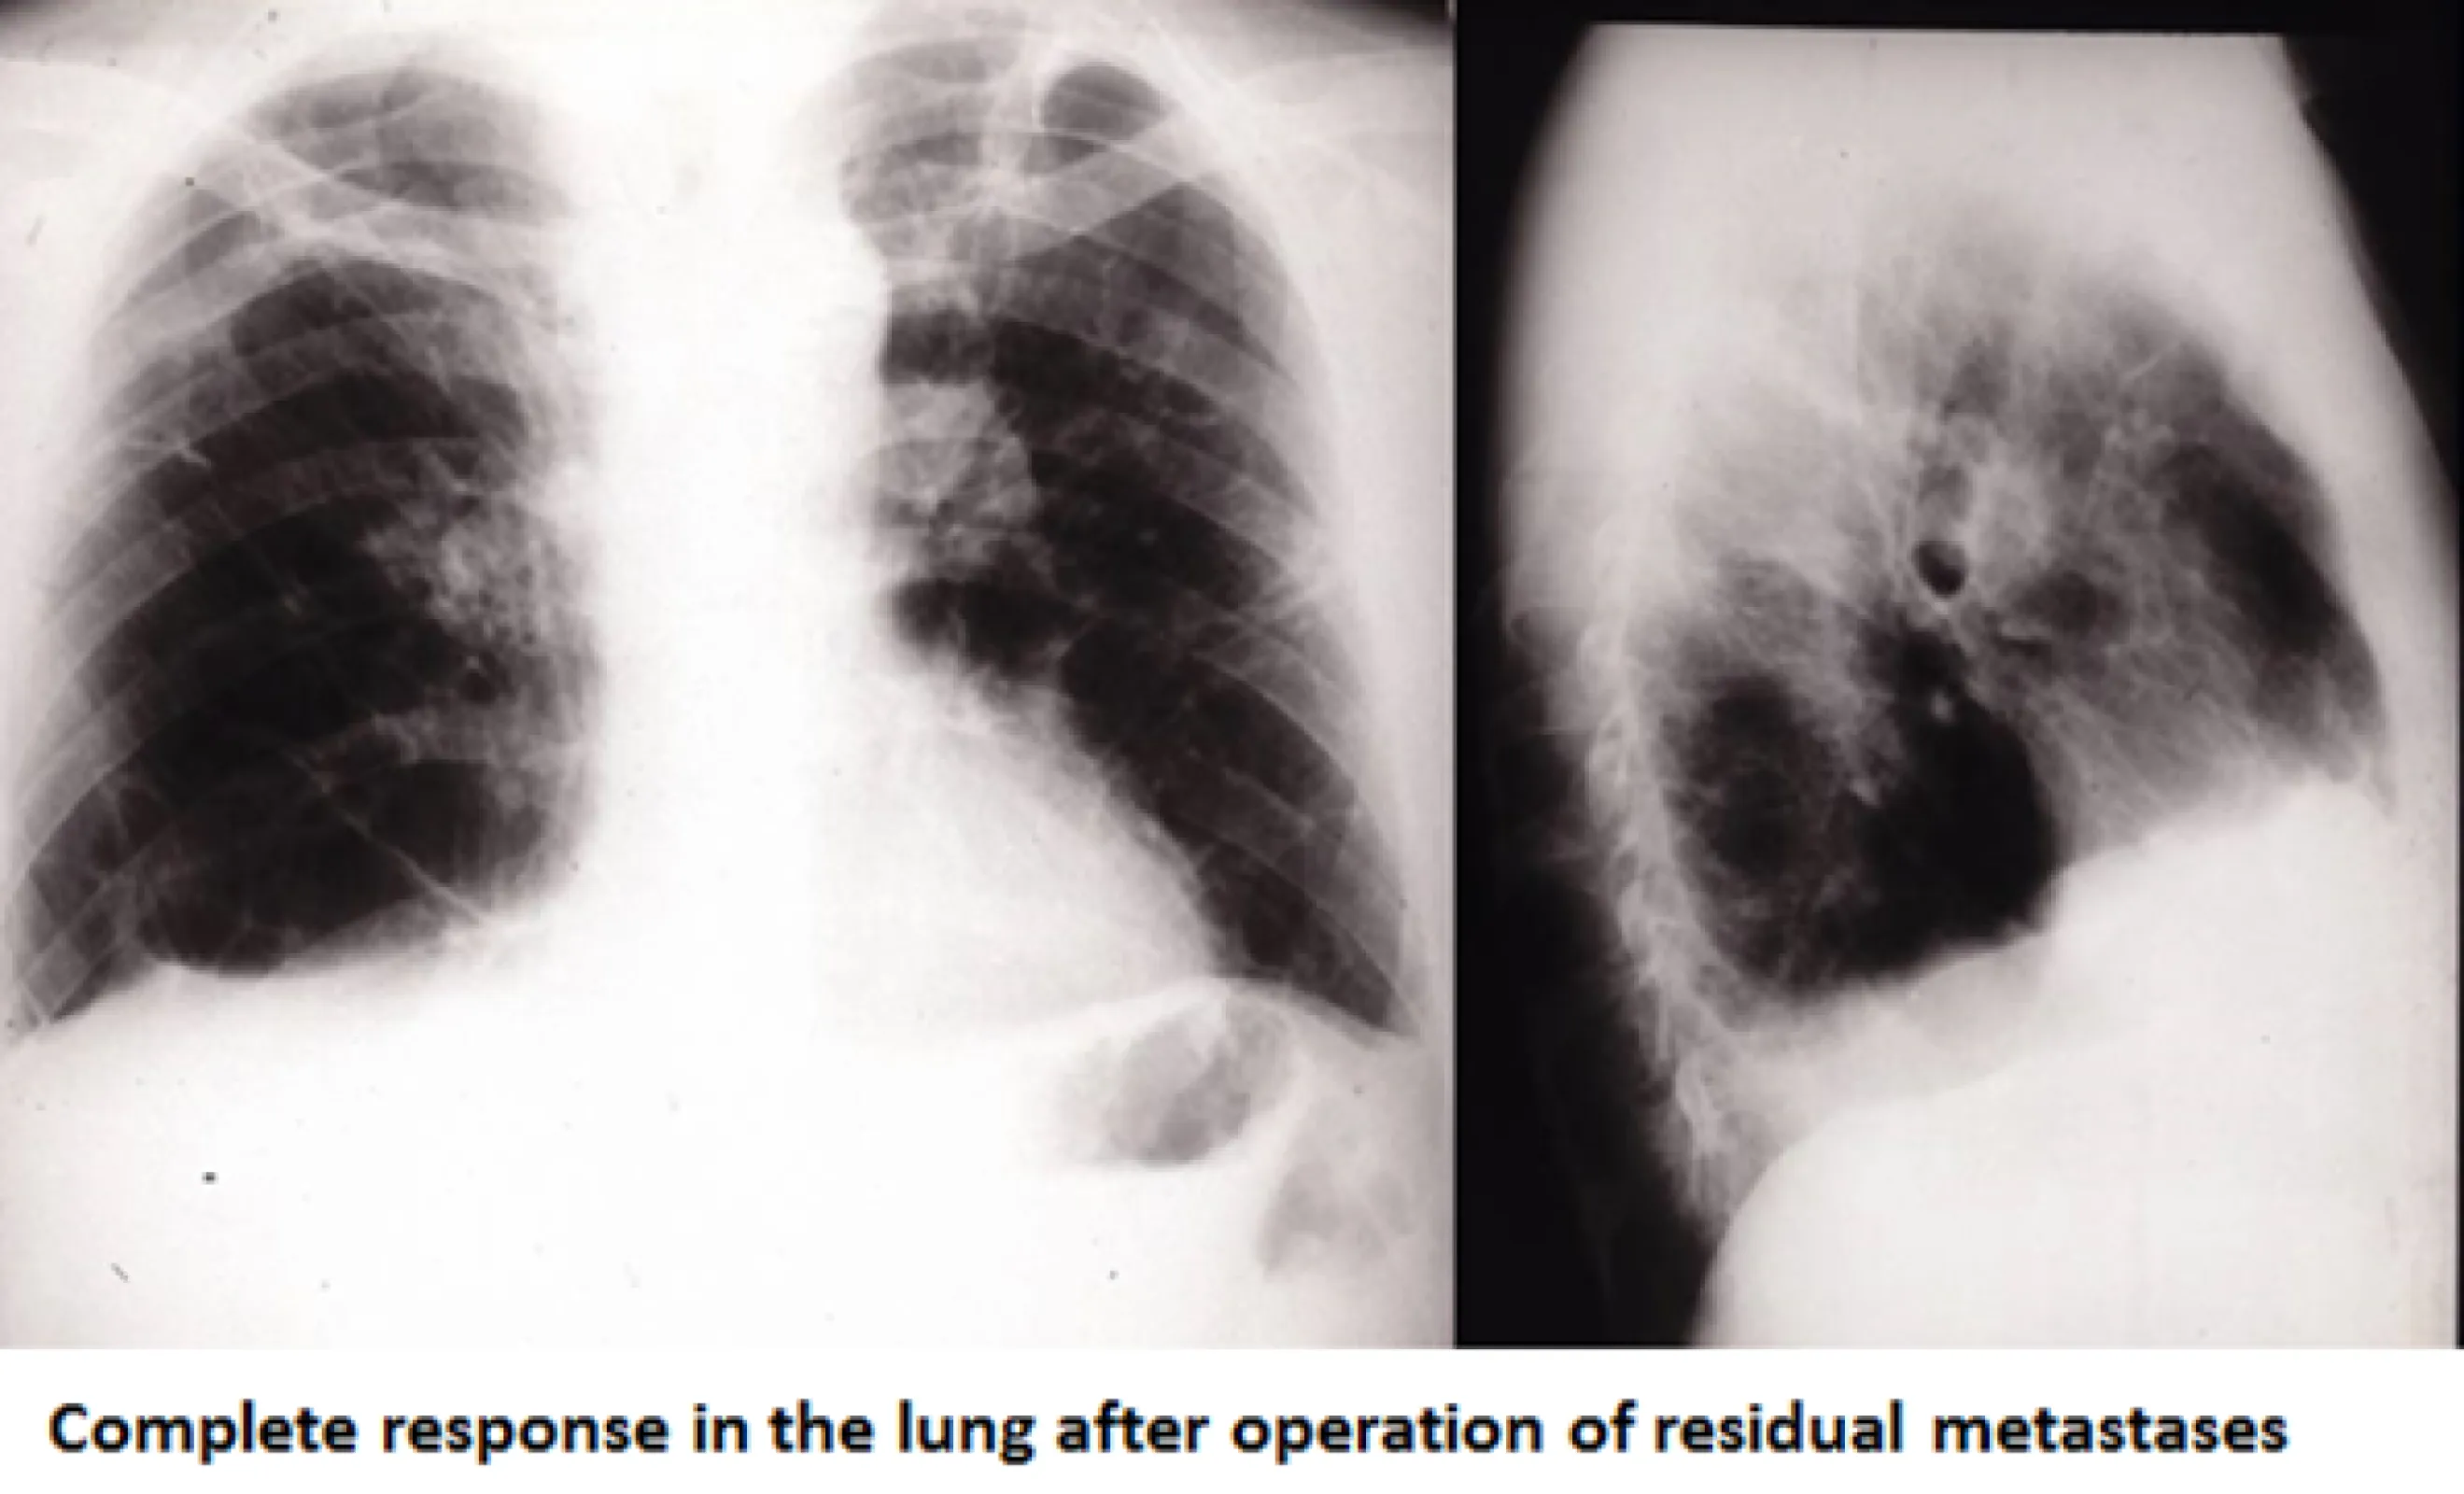

Patient X001 due to excellent response to IL-2inhalation therapy removal of all residual metastases was possible - complete response